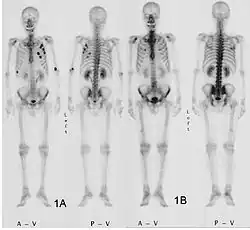

Ganzkörperknochenszintigramm mit 99mTc-HDP der Patientin mit der Oberarmfraktur aufgrund einer Brustkrebsmetastase